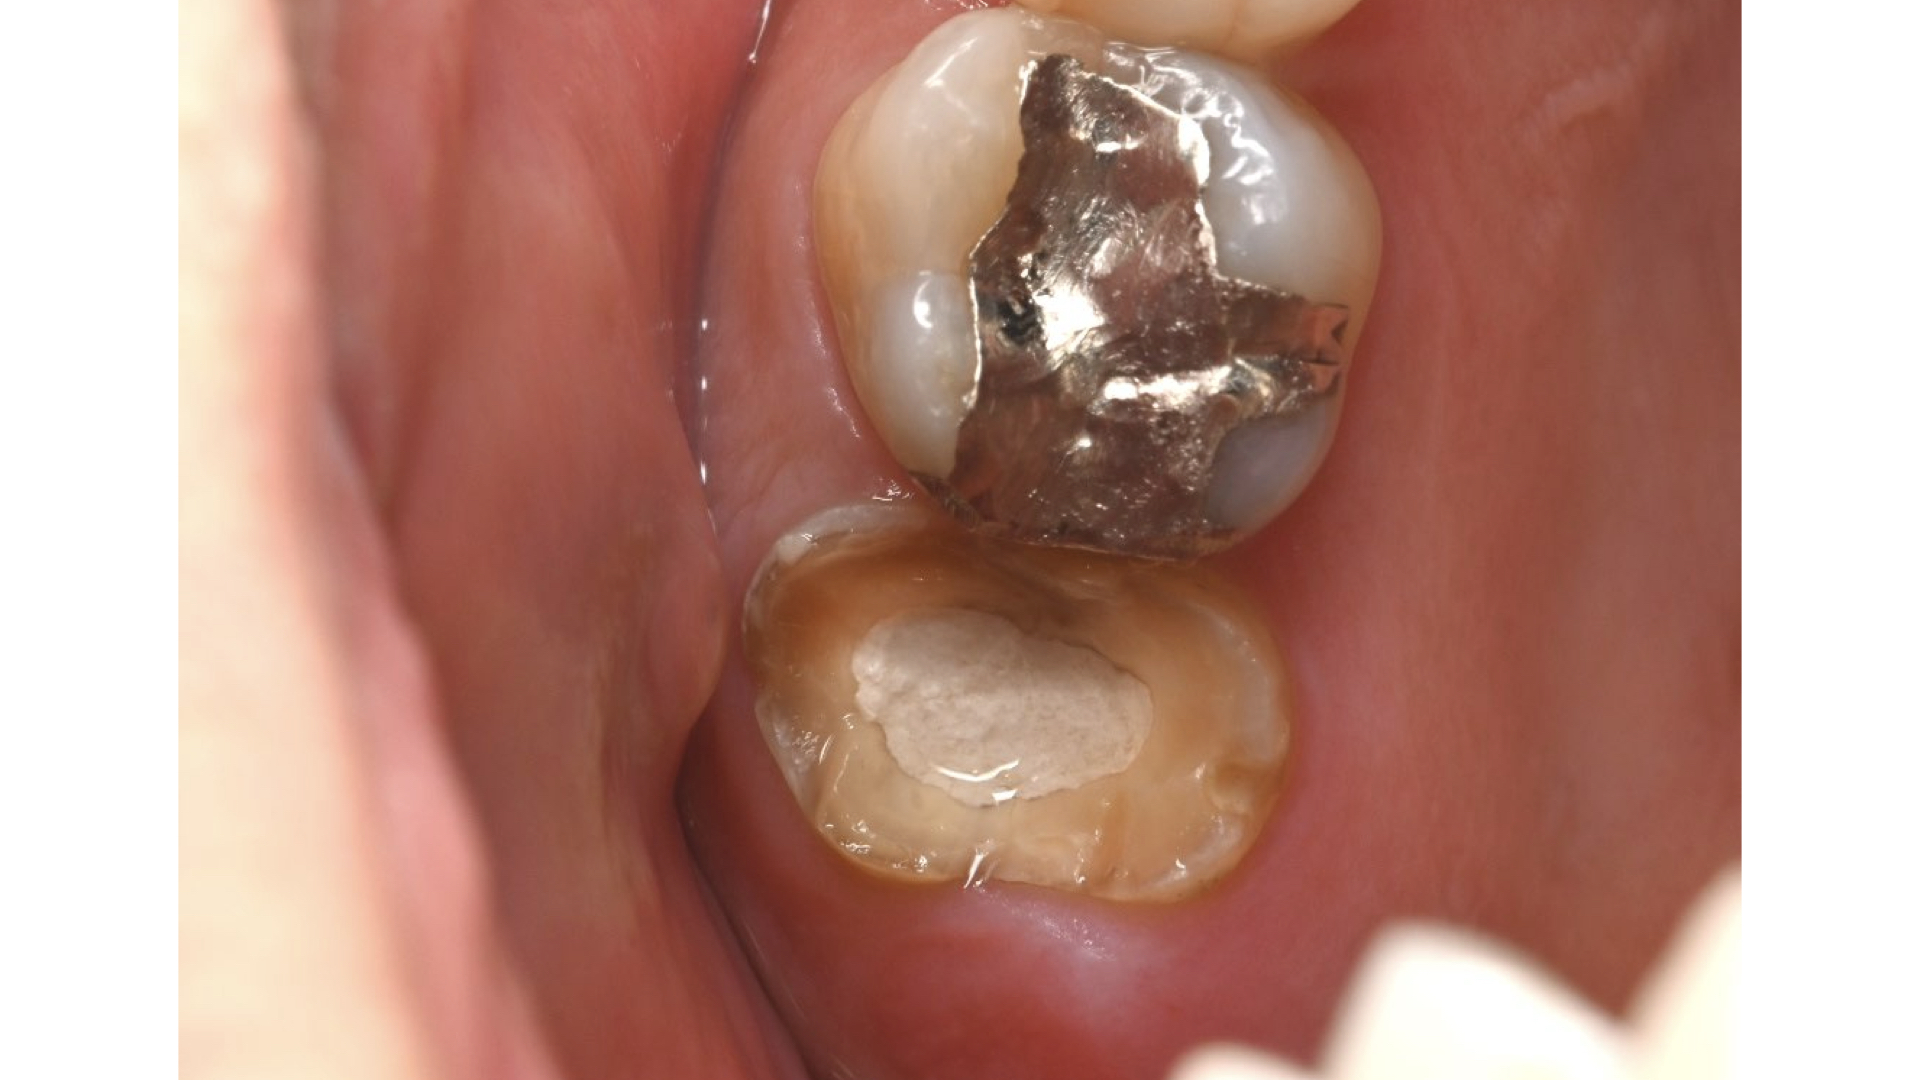

初診時

- 40歳 女性 パーソナルトレーナーさん

- 左上の奥歯の痛みで1年前に近医を受診、この時点で大学病院を勧められていた。治療に3ヶ月かかり、その後7ヶ月で再度炎症を起こした。抗生剤の服薬で収めていた。その後2ヶ月後に2回目の再炎症を起こした。抜歯または、大学病院を勧められた。大学病院は、3ヶ月後に初診を予約している。2回目の再炎症の際がピークで、左上を中心とした顔面の痛み、頭痛があった。抜歯と言われたが抜かない方法を考えている。歯の土台に太い金属が入っているため、治療方法、保険、自費根管治療の違いや歯の生存率も踏まえて知りたい。

- 歯の状態:歯質が骨縁上に適切な厚みを持って存在する。根尖の外部吸収様所見

- 歯根の外部吸収を伴う根尖性歯周炎

- 上顎洞炎を伴う根尖性歯周炎